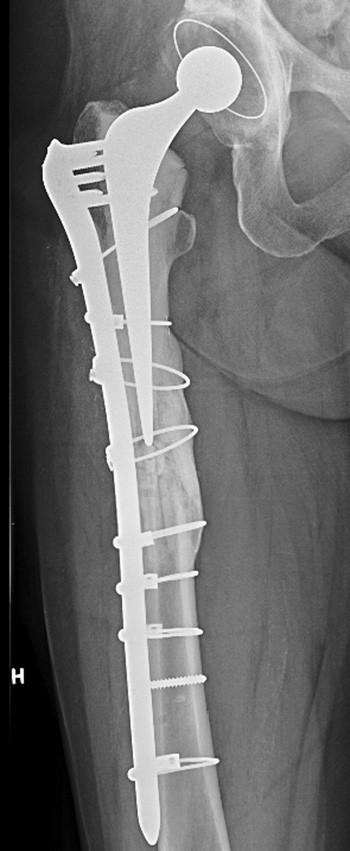

Ut ifra kunnskap om biologiske endringer i beinvev under påvirkning av bisfosfonater, bl.a. med nedsatt osteoklastaktivitet og dermed nedsatt remodellering, kan man regne med at frakturene oppstår som følge av at beinets kontinuerlige reparasjonsprosess er mangelfull. Mikrofissurer danner etter hvert større fissurer og ender som fraktur, under betegnelsen atypisk fraktur. Selv om de radiografiske kriteriene for atypisk fraktur og stressfraktur er like, er de patogenetisk helt forskjellige. Stressfrakturer oppstår ved sterk belastning av friske knokler over tid, slik man ser hos idrettsutøvere og militært personale.

Det er bred enighet om at periprotetiske femurfrakturer etter hofteartroplastikk helst behandles med intern fiksasjon (3). Det svenske hofteregisteret rapporterer 34 % svikt av osteosyntesene ved denne frakturtypen. Når frakturene dessuten er atypiske, vil komplikasjonsraten kunne tenkes å bli enda høyere. Atypisk femurfraktur som oppstår periprotetisk, er ikke omtalt tidligere, så vidt vi kan se. Det gir ytterligere økt usikkerhet rundt prognosevurdering og behandlingsvalg.

Spesielt designede plater som gir en dynamisk kompresjon og som tillater at skruene settes vinkelstabilt og med ulik vinkel på platen, sikrer stabiliteten i konstruksjonen, samtidig som implantatet ikke kommer i konflikt med protesekomponenter eller sementmantel. Alternativt kan kabelcerclage erstatte en eller flere skruer. I løpet av det siste tiåret er det også utviklet platesystem som gjør det mulig å koble små endeplater til hovedplaten, proksimalt og/eller distalt, for å dekke hele femurs lengde. Adekvat fiksasjon av frakturen kan oppnås med bruk av disse implantatene, kombinert med strukturelle, kortikale transplantat formet som plater, og dessuten bruk av spongiøse beintransplantat (chips).

Denne behandlingsstrategien ble først implementert i sin helhet ved de kirurgiske revisjonene hos vår pasient og førte til at frakturene omsider helet.

Frakturlinjen ved atypiske frakturer er oftest helt horisontal eller viser en vinkling på maksimalt 30 grader (2). Figur 1 i artikkelen viser imidlertid en frakturlinje som har en vinkel som er over 30 grader, slik at jeg ikke mener den kan klassifiseres som atypisk. Jeg mangler også i den forbindelse opplysninger om skjelettstatus hos denne pasienten med multiple brudd. Hadde den langvarige bisfosfonatbehandling hatt effekt eller var pasienten fortsatt osteoporotisk? Hvis sistnevnte var tilfellet, burde man ha overveiet osteoanabol terapi med PTH, som pasienten kunne få på blå resept.